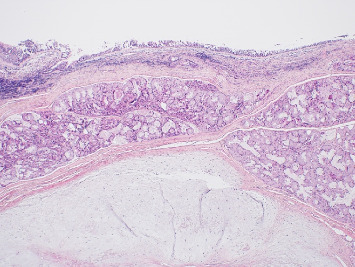

目的:本病例报告描述了一个罕见的扁桃体窝内的口腔软骨绒毛瘤,强调了识别和区分这种不常见的实体与更常见的口腔病变的重要性。方法:对一位30岁男性患者进行了全面的临床和组织病理学检查,他表现为鼻咽部无痛性肿块。进行了切除活检,并进行了组织病理学分析,以建立明确的诊断。结果:组织病理学检查显示为软骨性脉络瘤,其特征是结缔组织包围着成熟的透明软骨。患者接受手术切除病变,随访评估显示良好的术后结果,无复发。结论:口腔软骨脉络膜瘤极为罕见。意识到这个实体是至关重要的准确诊断和适当的管理,因为它可以模仿其他更常见的口腔病变。本病例报告补充了关于口腔软骨脉络瘤的有限文献,并强调了在口腔粘膜肿块鉴别诊断中考虑这一实体的重要性。

Objective: This case report describes a rare presentation of a cartilaginous choristoma of the oral cavity within the tonsillar fossa, emphasizing the importance of recognizing and differentiating this uncommon entity from more frequently encountered oral lesions. Methods: A comprehensive clinical and histopathological examination was conducted on a 30-year-old male patient who presented with a painless mass in the nasopharynx. An excisional biopsy was carried out, and a histopathological analysis was conducted to establish a definitive diagnosis. Results: Histopathological examination demonstrated a cartilaginous choristoma, characterized by the presence of mature hyaline cartilage surrounded by the connective tissue. The patient underwent surgical excision of the lesion, and follow-up assessments indicated a favorable postoperative outcome without recurrence. Conclusion: Cartilaginous choristomas in the oral cavity are exceedingly rare. Awareness of this entity is crucial for accurate diagnosis and appropriate management, as it can mimic other more common oral lesions. This case report contributes to the limited literature on oral cartilaginous choristomas and underscores the significance of considering this entity in the differential diagnosis of oral mucosal masses.